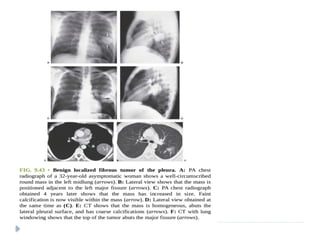

Pleural tumors / Masses

SOLITARY FIBROUS TUMOR OF PLEURA (SFTP)

 Also known as localized fibrous tumor or localized pleural

mesothelioma.

 45- 60 yrs

 Most of the tumors are benign; 20 % cases – malignant.

 Arises from visceral pleural in 80 %

 ON IMAGING :

 Soft tissue pleural-based neoplasm

 Areas of necrosis, hemorrhage, and cystic changes.

 Calcification may be seen in up to 26% of cases.

 Heterogeneous enhancement is seen post-contrast.

 On magnetic resonance imaging (MRI), hypointense solid mass is

seen on T1- and T2-weighted images. Necrosis and cystic

degeneration changes show high T2 signal intensity.

Benign pleural fibroma.

Enhanced CT reveals a soft tissue

intrafissural mass with coarse

calcifications, pathologically consistent

with a benign pleural fibroma.

Features of malignant fibrous tumor include : presence of

calcification, effusion, atelectasis, mediastinal shift , and chest wall

invasion.